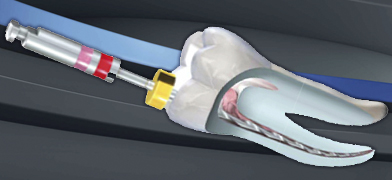

La compleja anatomía del sistema de conductos radiculares ha exigido a los endodoncistas utilizar para la fabricación de sus limas, materiales inteligentes y con propiedades sorpre

Fernando Durán, endodoncista y profesor de la Universidad de Internacional de Cataluña, nos cuenta en este video los detalles sobre el Motor de Endodoncia iRoot Pro